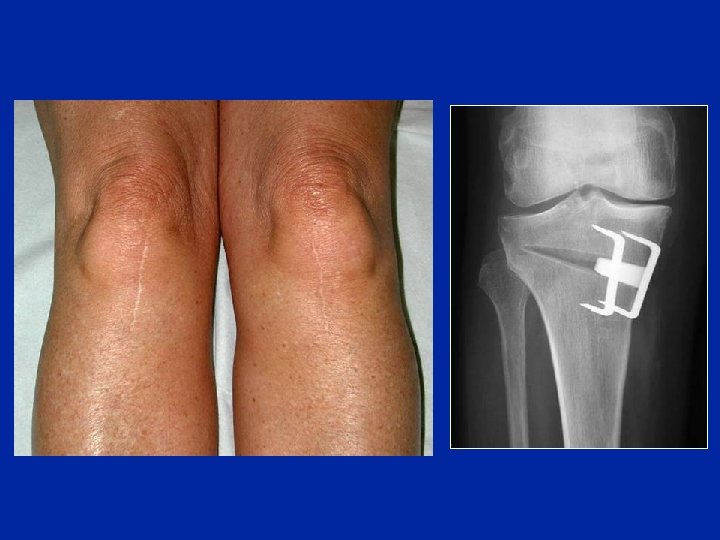

Ostéotomie d’ouverture interne Avantages – – – Simplicité Pas d’ostéotomie du péroné Pas de paralysie du SPE (aucune sur 428 ouvertures) Mobilisation précoce du genou 12 ans

Ostéotomie d’ouverture interne Inconvénients – – – Nécessité d’interposer un greffon Consolidation lente L’appui est retardé Pertes angulaires par tassement Allongement du membre Abaissement relatif de la rotule

Post-op 1 an 3 ans Ostéotomie d’ouverture avec un substitut osseux (Biosorb ®) Valgus 4°